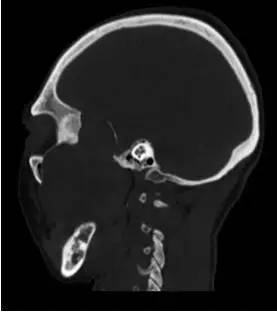

【病例】颞下窝区神经鞘瘤1例CT及MR影像表现

CT平扫矢状位重建

解析:本病例为中颅窝至颞下窝沟通性病变,对周围骨质主要呈膨胀压迫性改变,伴囊变、出血。

病理:(中颅底内外沟通肿瘤) 神经鞘瘤,伴出血,局灶细胞较丰富。免疫组化结果显示:EMA(-), P53(-), S100(3 ), NF(-), PR(-), desmin(-), Ki-67( ,5-10%)

神经鞘瘤